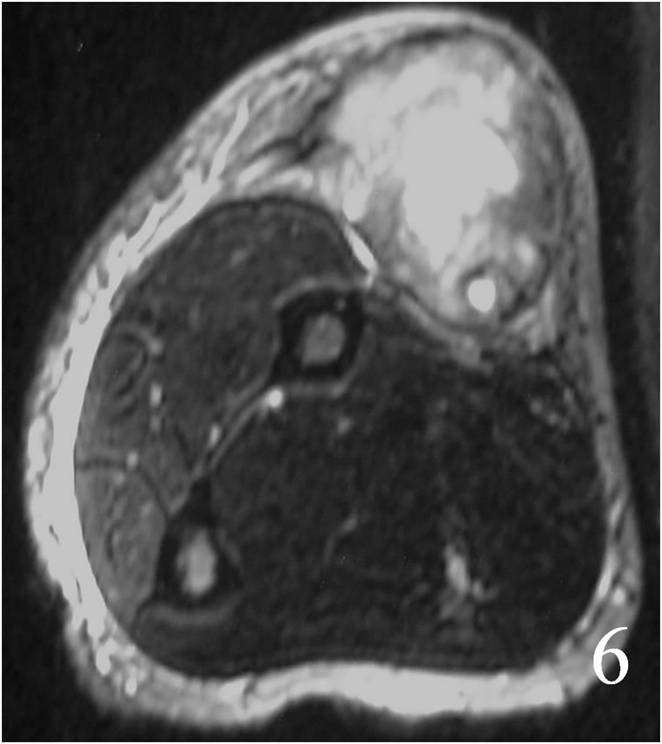

MRI

Nonspecific nonfatty mass (Fig. 2,3)

Large heterogeneous mass (Fig. 4, 5, 6)

Fig. 4 MRI of a leiomyosarcoma of the forearm shows a mass isointense to muscle on T1W image, heterogeneous on T2W (Fig. 5) and enhances with contrast T1W fat suppressed (Fig. 6)